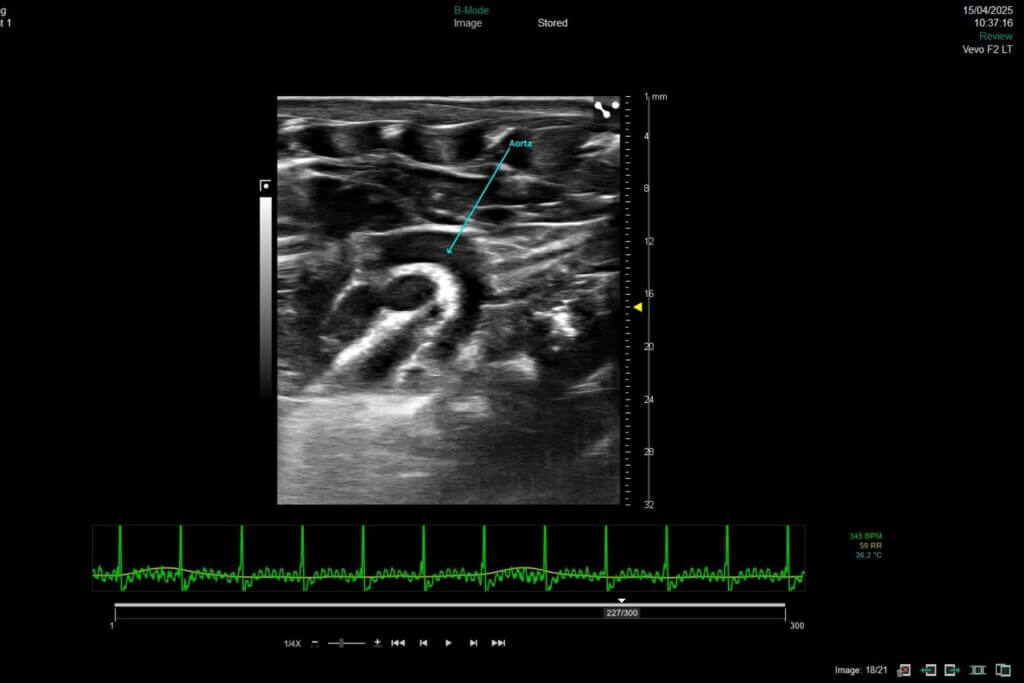

Left heart failure is characterized by an impaired ability of the heart to deliver sufficient cardiac output to meet the demands of the systemic circulation. It results from chronic hemodynamic stress, such as increased afterload, or ischemic myocardial injury, and is associated with progressive structural and functional cardiac remodeling.

Our platform enables the direct evaluation of therapeutic candidates in both HFrEF and HFpEF models, integrating comprehensive assessments of left ventricular function by echocardiography, cardiac remodeling, and cardio-renal-metabolic interactions.

Permanent coronary artery ligation model

The permanent left coronary artery ligation model is based on the definitive ligation of this artery, inducing a large myocardial infarction and progressive left‑ventricular failure. It recapitulates key mechanisms of post‑infarction remodeling: necrosis, inflammation, fibrosis, and long‑lasting impairment of cardiac function. This model is a robust tool for evaluating cardioprotective, antifibrotic, or regenerative therapies.

Ischemia-reperfusion injury model (IRI)

The myocardial ischemia–reperfusion (IRI) model consists in transient occlusion of the left coronary artery to reproduce the damage caused by tissue reperfusion following a treated myocardial infarction. This approach generates massive oxidative stress, acute inflammation, significant apoptosis, and early myocardial remodeling. This model provides an ideal platform for evaluating cardioprotective, antioxidant, or anti‑inflammatory therapies targeting reperfusion‑induced injury.